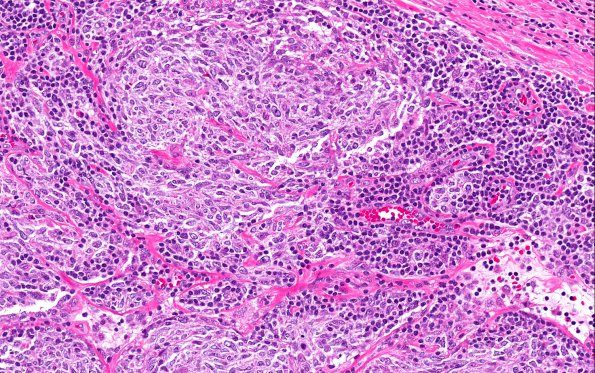

28A3 Lymphoma, B-cell, spindle-sclerosing variant (AANP 2016-Case 4) 20X

Higher magnification of the specimen (H&E)